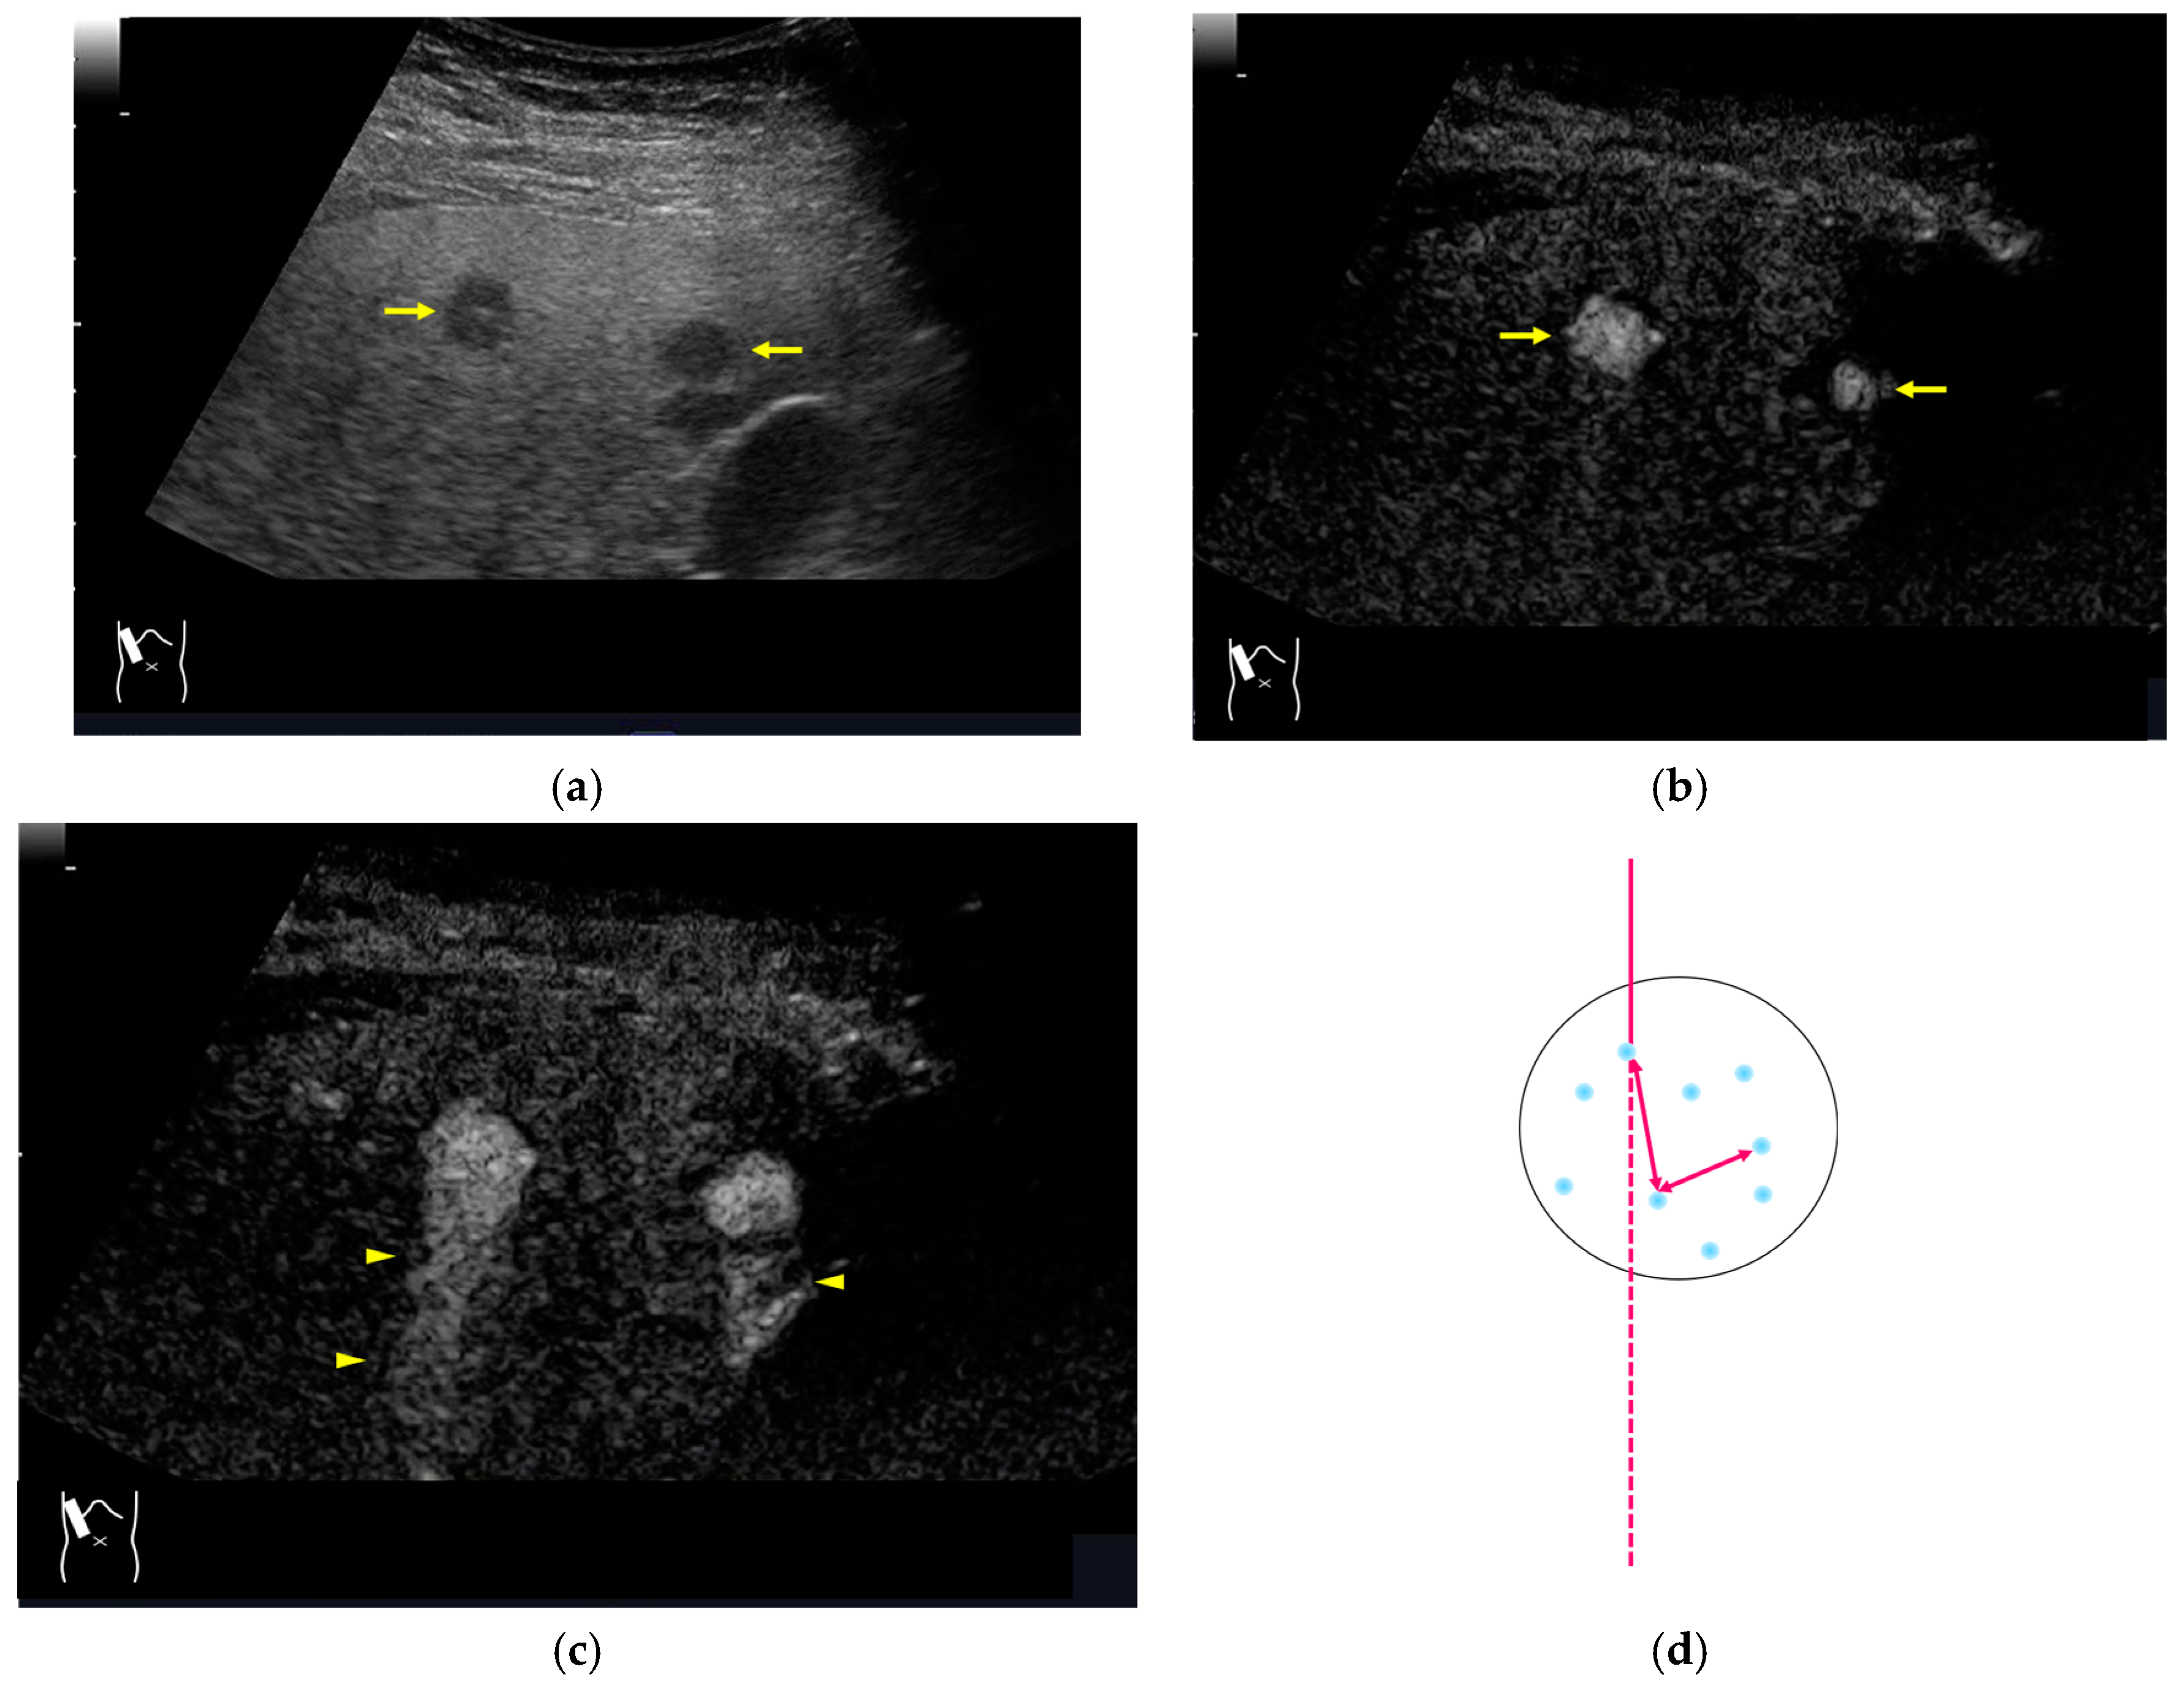

3.2.3. CEUS-Related Posterior Echo Enhancement

CEUS-related posterior echo enhancement (PEE) differs from that of B-mode US. PEE is the most easily recognizable US artifact, and it is characterized by an echogenic band behind a lesion with sonographically different characteristics. In B-mode US, PEE is thought to be secondary to changes in the attenuation of US beams. The area distal to a less attenuating lesion exhibits an increased US intensity and is brighter than it would be without the lesion [60,61]. Posterior echoes are also considered to be strongly related to sound refraction, which occurs when the US beam strikes the interface between two media with different acoustic velocities at an oblique angle of incidence [62]. Whether the US beams converge or diverge depends on the form of the interface and whether the sound path is from a high-velocity medium to a lower-velocity medium or the opposite. The latter condition is thought to give rise to PEE. Aside from these well-known causal factors, there are many other factors contributing to PEE, including reverberation. In brief, PEE remains a multifaced entity featuring complex interplay among sound attenuation, sound refraction, sound reverberation, and other factors. In the clinical setting, hemangioma [63], hepatocellular carcinoma [61], and hepatic cysts are known to cause PEE. We sometimes encounter CEUS-related PEE in daily CEUS examinations. It is characterized by the sudden appearance of a highly echoic zone during CEUS at a location where there was no highly echoic zone in B-mode US (Figure 14). Although this phenomenon’s mechanism of appearance has not been fully elucidated, the most plausible explanation is that many scattered signals emitted from the contrast agent, which rapidly flow into the lesion, interfere with each other inside the stained area, and the reflected time-delayed signals return to the transducer with a certain delay, resulting in the appearance of a highly echoic zone behind the lesion. The precise mechanism of CEUS-related PEE is a problem to be resolved in the near future.

Figure 14.

Posterior echo enhancement appearing during CEUS. (a) Gray-scale US of the case (arrows). (b) CEUS image of the lesion (focal nodular hyperplasia) (arrows). (c) CEUS image of posterior enhancement (arrow heads). Posterior echo enhancement appears immediately after the mass is rapidly and homogeneously enhanced. (d) Reasonable explanation of this phenomenon. Many scattered signals emitted from the bubbles that rapidly enter the mass lesion interfere with each other inside the stained area, and these scattered signals return to the transducer with a certain time-delay. These time-delayed signals are displayed as a PEE. Black circle: mass lesion; small blue circles: CEUS bubbles; red solid line: ultrasound beam; red dashed line: ultrasound is expected to travel; red arrows: reflection between bubbles.